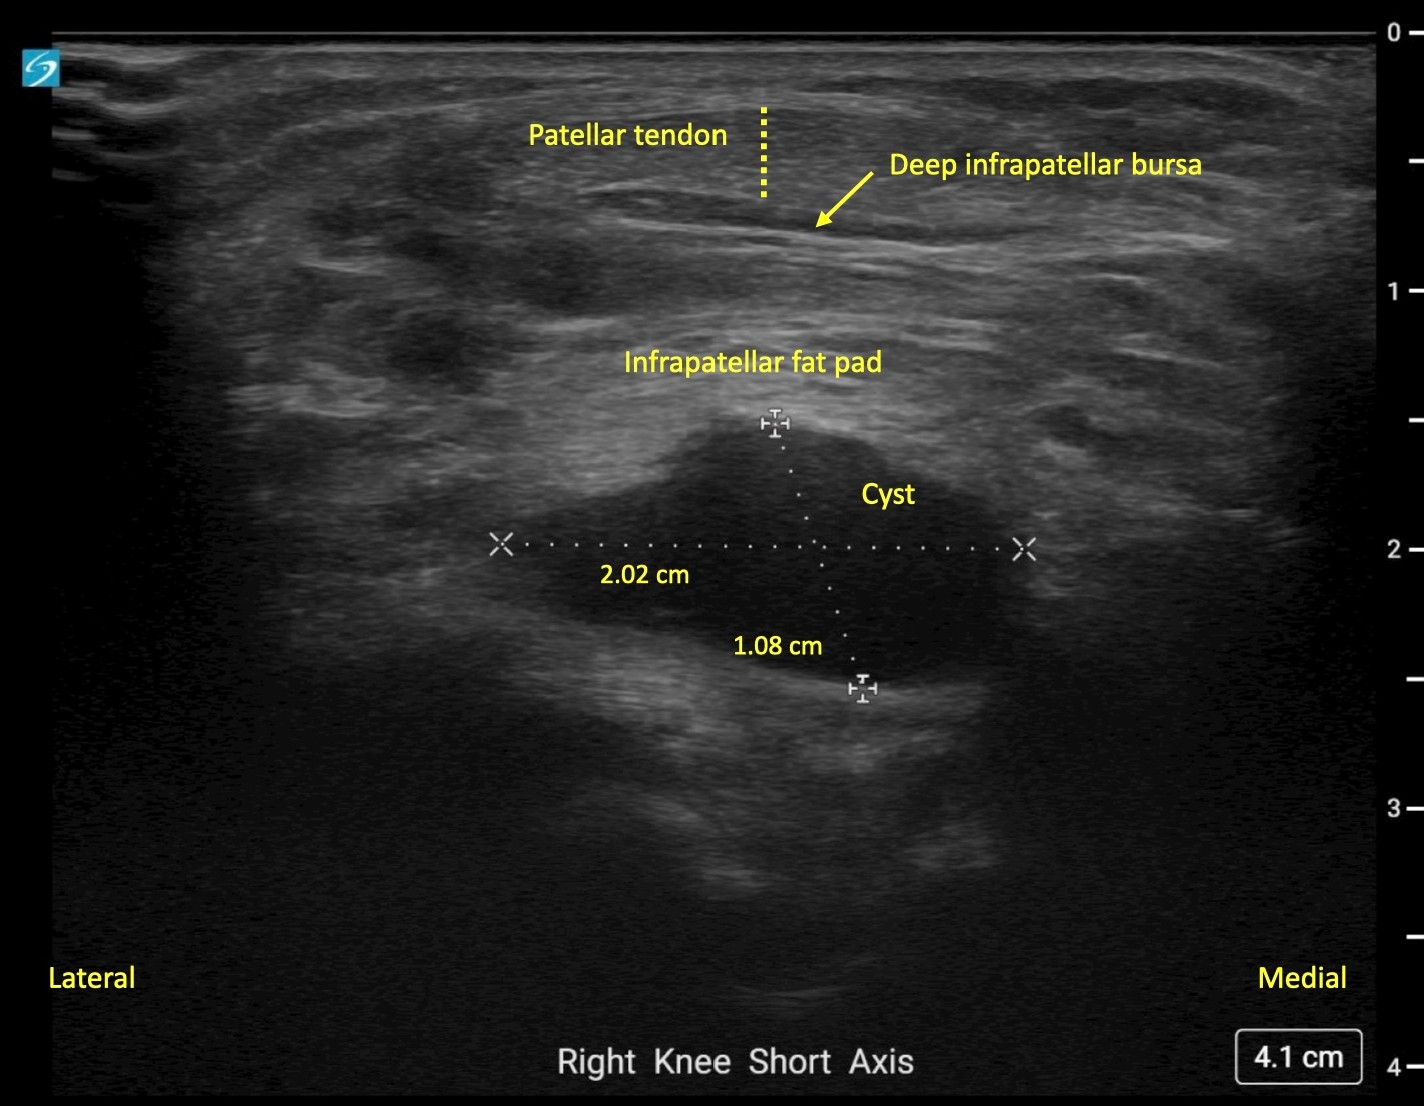

Image Interpretation: An anechoic, well-circumscribed, well-demarcated mass was noted deep to the infrapatellar fat pad. This measured 2.02 cm x 1.08 cm x 1.72 cm. No color Doppler flow was noted and the structure remained noncompressible when pressure was applied. A separate, smaller, anechoic mass was noted deeper to this structure and likely communicated with it. Findings were consistent with a multiloculated cyst of intra-articular origin.